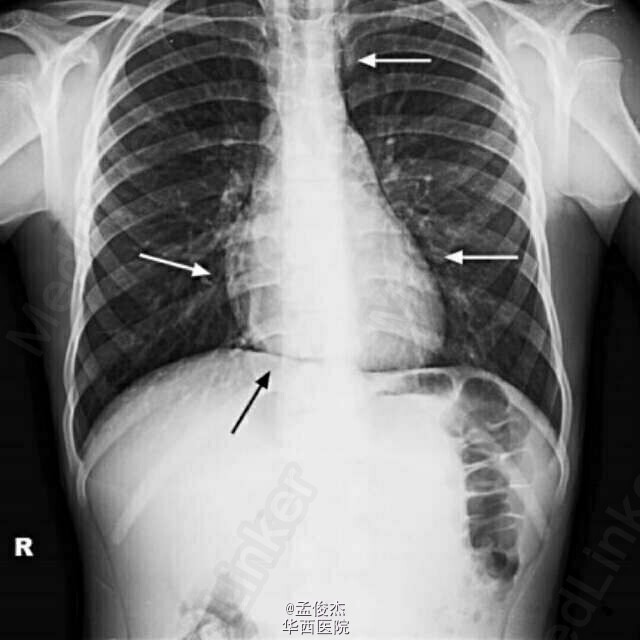

患者男性,11岁,在运动中摔倒,胸前壁受到橄榄球的挤压,背部受到3个人挤压。当时没有明显症状。2个小时后突感胸骨后剧烈痛入院。深呼吸或者咳嗽时胸痛加重,无哮喘胸廓疾病史。体格检查发现:心率74次/分,氧饱和度99%,呼吸24次/分,体温36.8℃,胸壁没有血肿,咽喉没有水肿,面部,颈部,胸背部也没有皮下气肿。胸骨未见骨折。未闻及哮鸣音。给予对乙酰氨基酚后疼痛显著减轻。 胸部平片发现纵膈和心包周围有气体,支气管镜排除论文气管和支气管损伤,心电图未发现明显异常。血常规和CRP未见异常。超声检查示心脏周围有游离气体。 给予头孢他啶7天预防感染,对乙酰氨基酚控制疼痛。疼痛在12h后缓解。3日后复查超声心动图显示气体被完全吸收。7日后复查胸片示气体完全吸收。第8天出院。 纵隔气肿和心包积气最常见的症状是胸骨后尖锐剧烈的疼痛,呼吸困难等。咳嗽,深呼吸,吞咽和平卧时症状加重。胸片即可诊断纵隔气肿和心包积气。 纵隔气肿和心包积气是橄榄球运动中非常罕见的损伤。在出现胸部创伤和疼痛时运动员和教练都应当警惕,尽量在1个小时候之内将伤员送到医院。治疗不及时会导致气体聚集增多,器官血管神经受压。